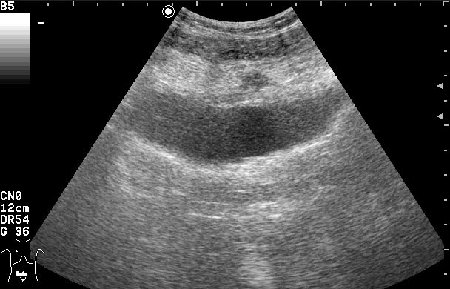

Женщина 42 лет с болями внизу живота, дизурическими явлениями, повышением температуры.

Сонограммы мочевого пузыря

Похоже на опухоль, но по анамнезу я больше склоняюсь к воспалению урахуса!

Согласна с первым постом-возможно нагноение урахуса(и клиника подходит)